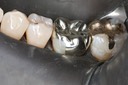

Gary Umeda #2,3

Gary Umeda #2,3 bitewing radiograph